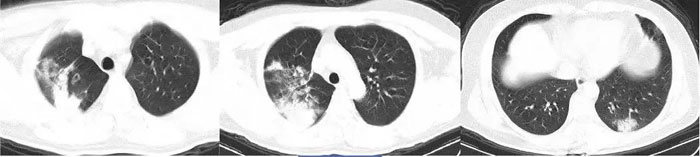

3分:局限的叶段病变,叶段小斑片影或多发小结节,提示肺部感染性病变(细菌或结核或其它病毒感染,也可能难于鉴别),有较小的新型冠状病毒感染的可能性。

临床意义:居家隔离和社区隔离,针对性抗菌或抗结核等治疗后复查;如治疗无效,核酸检测判断是否新型冠状病毒(2019-nCoV)感染。

4分:单个叶段的中心实变周围磨玻璃密度影,或双肺多发的小斑片或磨玻璃密度影,形态各异,提示肺部感染性病变,有较大的新型冠状病毒感染可能性。

临床意义:医院隔离治疗,申请核酸检测,阳性可确诊2019-nCoV感染。

5分:双肺胸膜下区多发斑片状磨玻璃密度影,边界清楚,可短期(几天内)演变为大片实变或者逐渐吸收、纤维化,强烈提示新型冠状病毒感染性肺炎。

临床意义:无论核酸检测是否阳性,依照2019新型冠状病毒(2019-nCoV)感染肺炎治疗,传染病病房隔离。亲密接触者隔离观察。